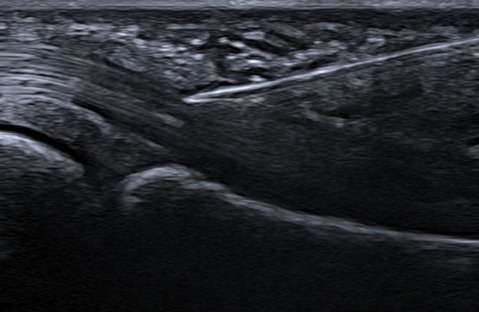

✔ Contrôle échographique en temps réel

Repérage précis à l’échographie

Ponction du liquide (si nécessaire)

Infiltration ciblée du traitement